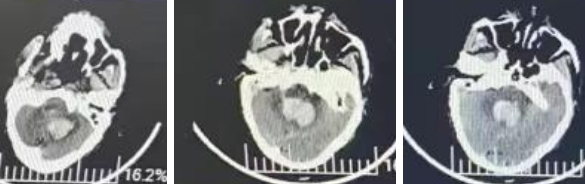

患者是一名老年男性,主要表现为突发意识障碍,头部CT示左侧小脑出血并破入到第四脑室,血肿体积20ml,压迫生命中枢脑干,同时引起脑积水(图1)。

图1